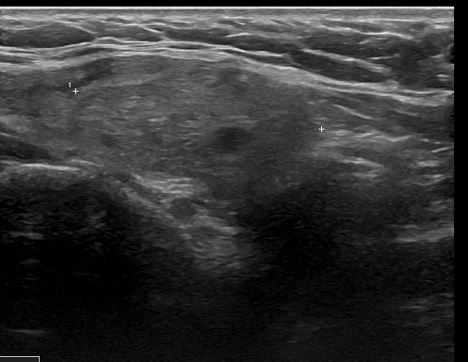

양성 결절로 진단받은 증례 130대 초반의 여성으로 오른쪽 갑상선에 2.7cm 결절이 관찰된다.

세침 흡인 검사 실시

베세다 시스템II에서 악성 가능성이 3% 미만인 양성 결절로 진단 받았습니다.양성 결절로 진단된 증례 2